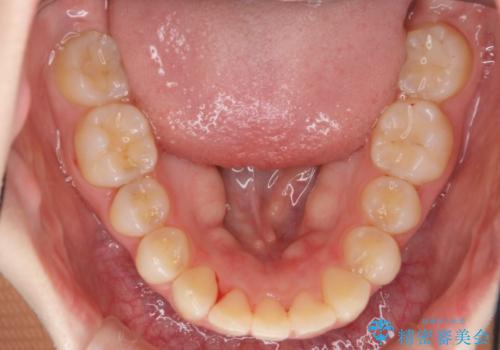

- 上の前歯が出ている感じを治したい、と矯正治療を希望され来院されました。

上顎歯列の突出感を改善すべくIPRを行い、下顎歯列を小さくすることで前歯の角度を大きく是正します、。

下顎歯列は元々前歯が1本少なく小さなアーチでしたが、下顎に合わせ上顎歯列もIPRを行い小さくすることで出っ歯感を大きく改善することが出来ました。